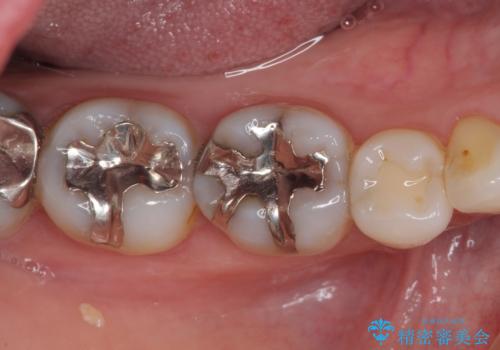

- 口を開けたときに目立ってしまう銀歯をセラミックに替えたいとのことで来院された患者様です。

上顎や親知らずにも銀歯がありましたが、今回の治療では目立つ下顎の銀歯4歯をセラミッククラウンやセラミックインレーに置き換えることにしました。